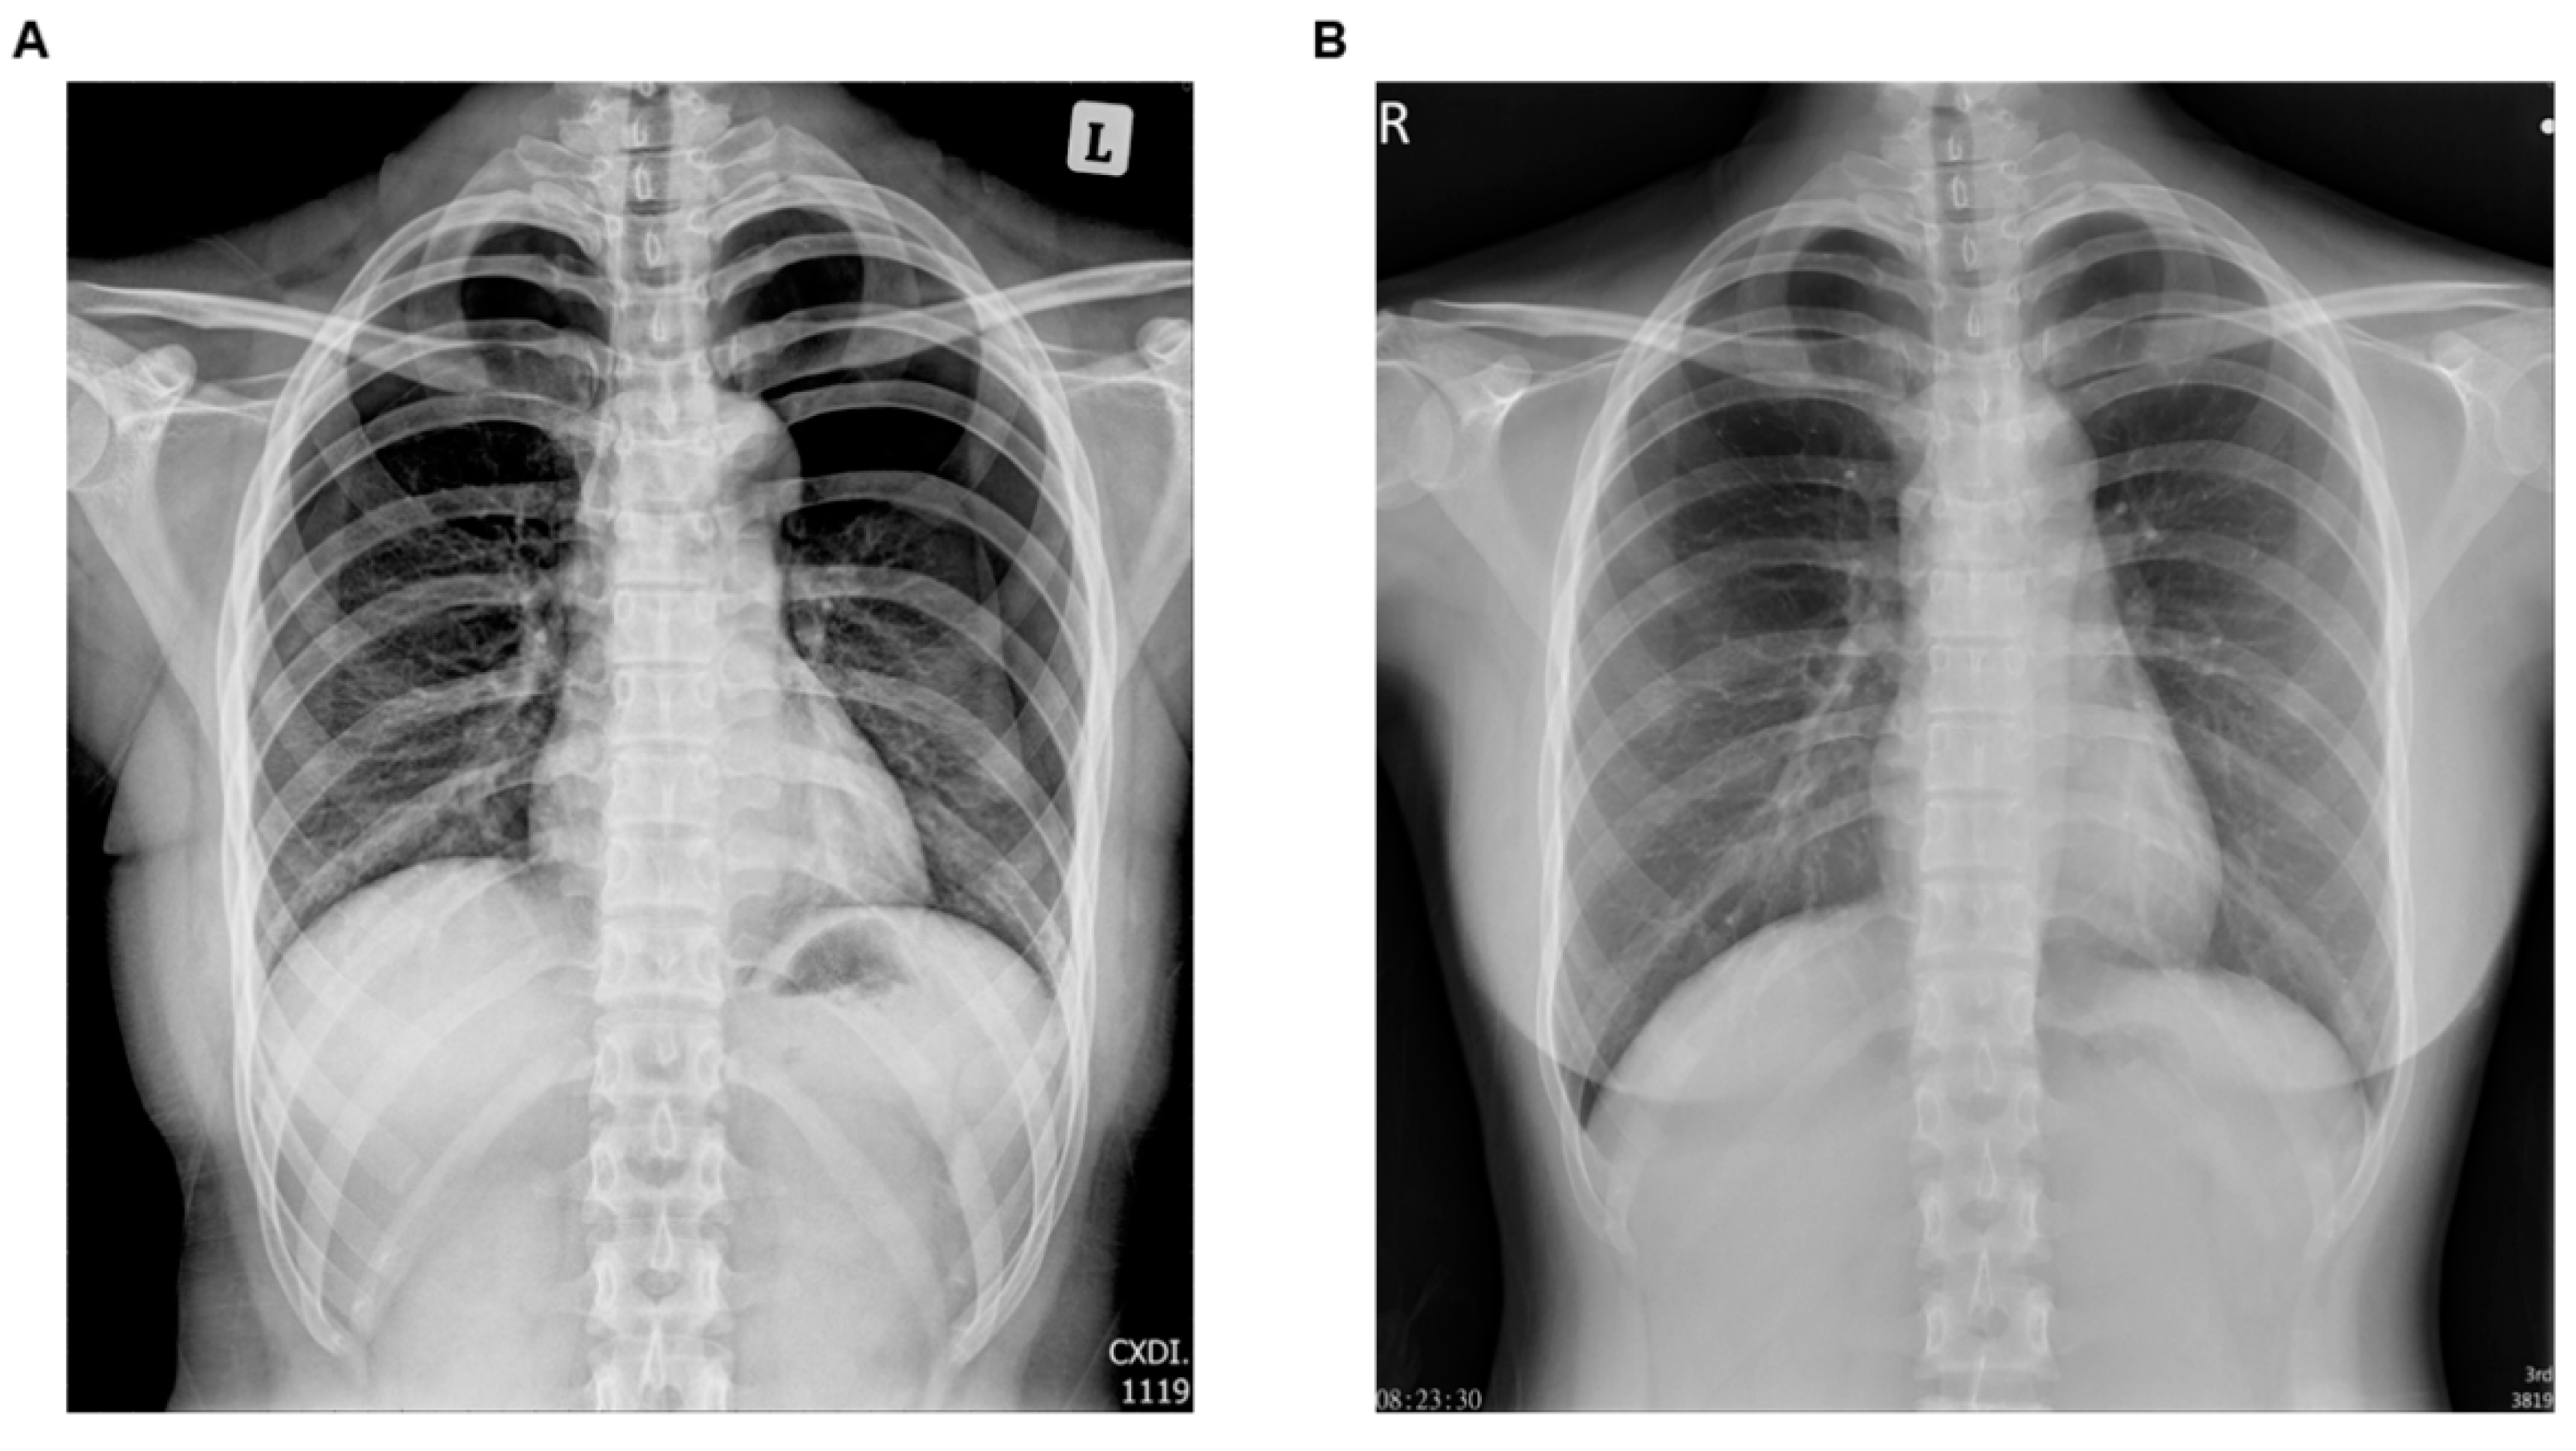

2.1. Case 1

2.2. Case 2